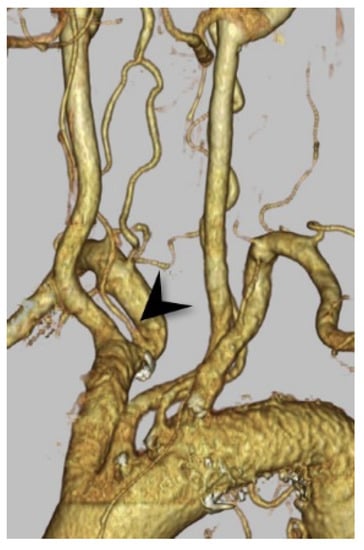

3.2. Right VA Originating from the Common Carotid Artery or the Brachiocephalic Artery